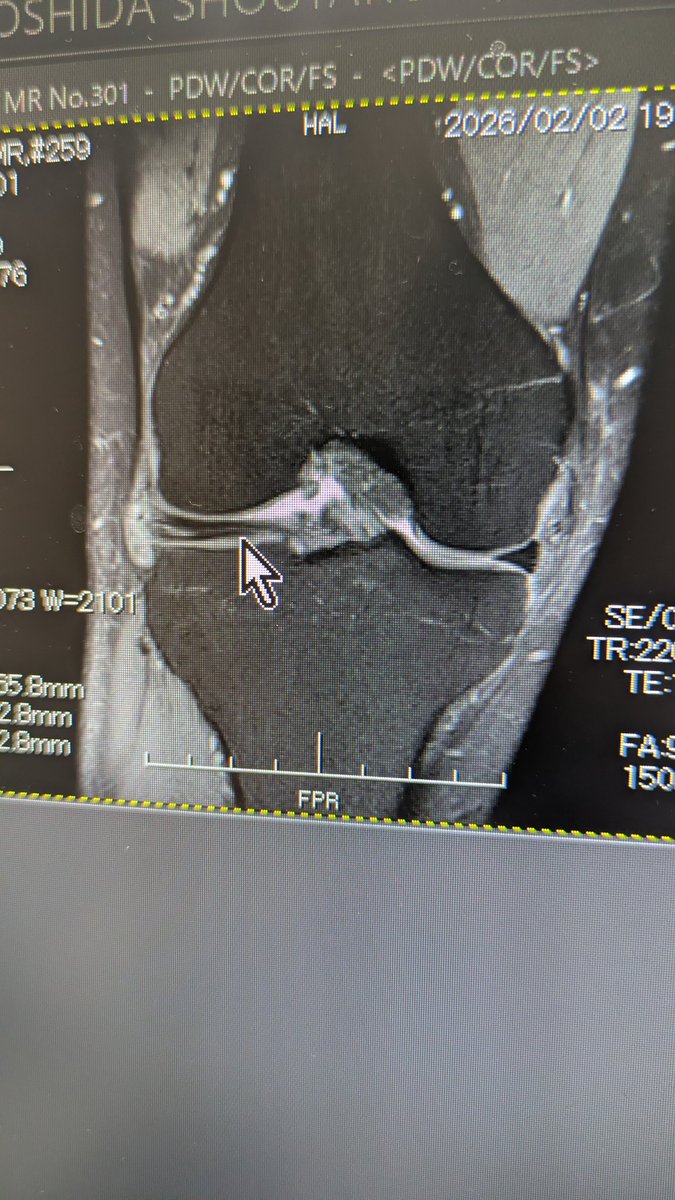

円盤状半月に加えて水平断裂

トリミングと縫合…となかなかハードめな様相